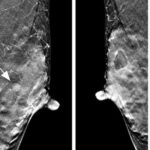

Dense breast: tomosynthesis vs MRI. And the winner is…

Dense breast is a challenge for the radiologist and especially for mammography. Can breast tomosynthesis reach the accuracy of MRI? In this study, the authors conclude that MRI may still be ahead for diagnostic performance. Article: The role of breast tomosynthesis in...